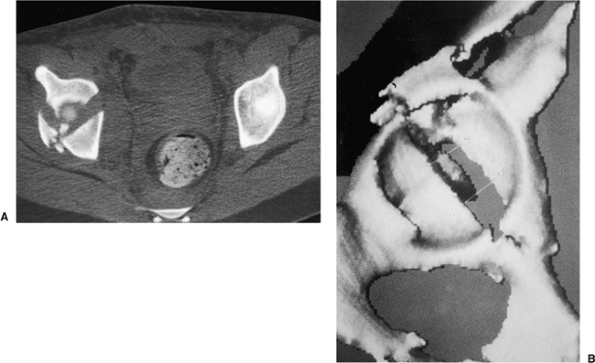

views provide additional information about the extent of injury to the

acetabulum (Fig. 43.6A), especially

identification of posterior-wall fractures, rotation of the columns,

the presence of intra-articular fragments or femoral head fractures,

and the assessment of articular displacement. Axial CT

scans

also can identify associated injuries to the posterior aspect of the

pelvis, such as a sacroiliac-joint disruption and sacral fractures.

Thin (1 to 2 mm) cuts should be used, along with sagittal and coronal

reformatting, to evaluate thoroughly the fracture pattern

preoperatively. Advances in imaging software technology have led to the

development of three-dimensional CT, which provides an even better

understanding of the spatial relation of the fracture pattern relative

to the pelvis (see Fig. 43.6B).

![]() |

|

Figure 43.6. CT of pelvis of patient in Figure 43.3. A. Axial view revealing significant dome comminution. B. Three-dimensional reconstruction facilitating perception of configuration.